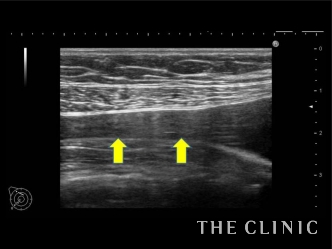

矢印で指している部分が破損したバッグから流れ出した内容物なのですが、鎖骨近くまで漏出していることが確認できます。